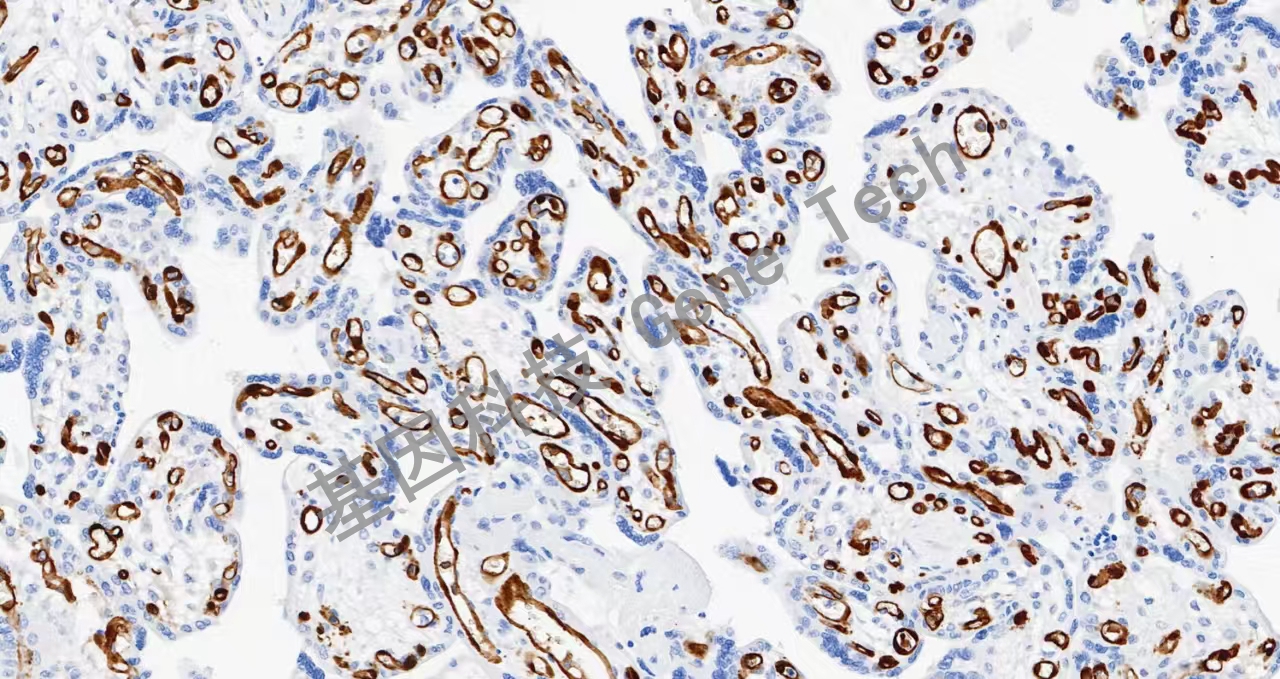

| 簡介:IDO1(吲哚胺2,3-雙加氧酶)是一種含血紅素的酶,在許多組織和細(xì)胞中生理表達(dá),如小腸、肺、胎盤。IDO1是免疫系統(tǒng)的重要組成部分,在對抗各種病原體的自然防御中發(fā)揮作用。它通過在樹突狀細(xì)胞、單核細(xì)胞和巨噬細(xì)胞中表達(dá),調(diào)節(jié)T細(xì)胞的行為。最近的研究表明,IDO1在腫瘤發(fā)展過程中被激活,幫助惡性細(xì)胞逃脫免疫系統(tǒng)的根除。IDO1在多種類型的癌癥中表達(dá),如卵巢癌、結(jié)腸癌等。 | ||

| 胎盤石蠟切片,用 IDO1(GT2296)染色,細(xì)胞漿/細(xì)胞核陽性,DAB 顯色。 | ||